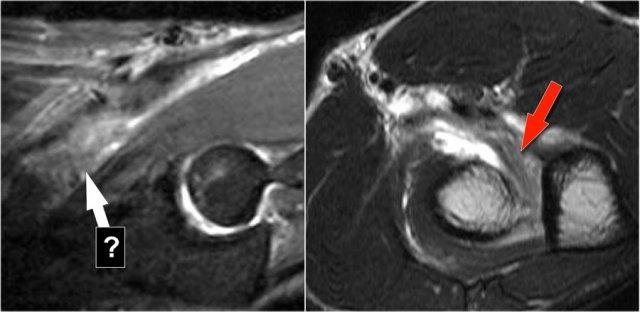

Radiobicipital bursitis

Đây là các hình ảnh mặt phẳng đứng dọc và mặt phẳng ngang của một bệnh nhân được chuyển đến bác sĩ phẫu thuật ung thư chỉnh hình vì một khối u gần khuỷu tay.

Có một vết rách một phần (mũi tên) của gân cơ nhị đầu, nhưng câu hỏi đặt ra là, cấu trúc mà chúng ta đang quan sát là gì và bên trong nó chứa gì.

Cấu trúc này là túi hoạt dịch quay-nhị đầu, vì vậy đây là viêm túi hoạt dịch.

Cần nhớ rằng gân cơ nhị đầu không có bao gân, do đó viêm bao gân không phải là khả năng có thể xảy ra.

Chẩn đoán phân biệt cho các cấu trúc cường độ thấp trong túi hoạt dịch bao gồm: chondromatosis màng hoạt dịch, viêm màng hoạt dịch thể sắc tố dạng nốt (PVNS) và thể hạt gạo.

Hóa ra đây là các thể gạo (rice bodies).

Here another case.

Mũi tên trắng trong hình bên trái đang chỉ vào túi hoạt dịch.

Lưu ý rằng cơ nhị đầu vẫn còn nguyên vẹn.

Bên cạnh túi hoạt dịch quay-nhị đầu (mũi tên vàng), một túi hoạt dịch gian cốt (mũi tên đỏ) cũng đã được Abdalla Skaf mô tả trên tạp chí Radiology trong bài báo có tiêu đề: Viêm túi hoạt dịch nhị đầu-quay: Các dấu hiệu trên hình ảnh MRI.

Đôi khi các khối này có thể giống u bướu hoặc có thể gây chèn ép dây thần kinh quay khi chúng trở nên rất lớn.